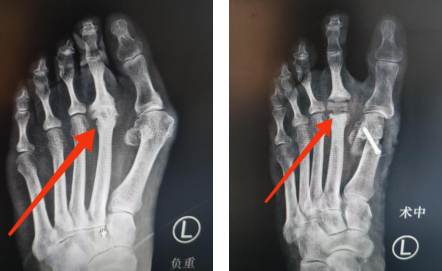

术前术后X光片对比

不仅置换了坏死的跖趾关节,消除疼痛,还矫正了阿姨的拇外翻,并且术后两天就可以下床行走。